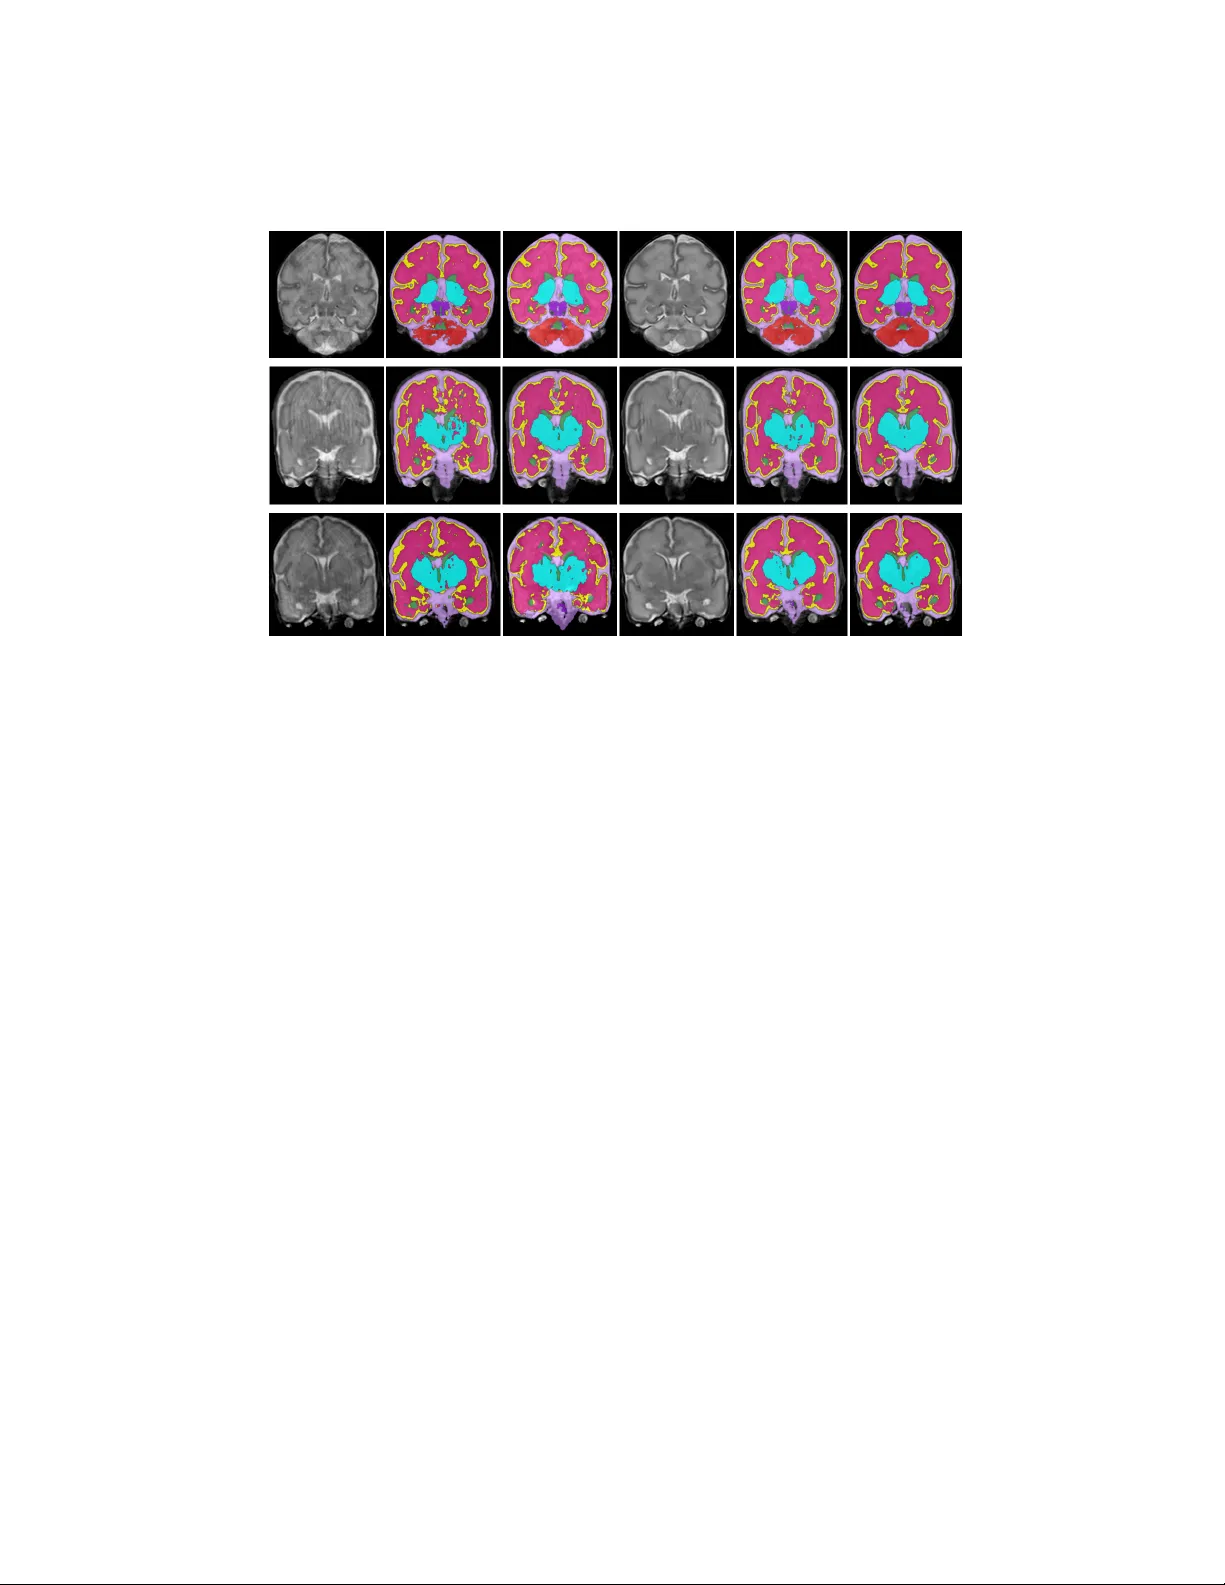

Generativ e adv ersarial net w ork for segmen tation of motion affected neonatal brain MRI N. Khalili 1 , E. T urk 2 , M. Zreik 1 , M.A. Viergev er 1 , 3 M.J.N.L. Benders 2 , 3 , and I. I ˇ sgum 1 , 3 1 Image Sciences Institute, Universit y Medical Center Utrec ht, The Netherlands 2 Departmen t of Neonatology , Wilhelmina Childrens Hospital, Universit y Medical Cen ter Utrech t, The Netherlands 3 Brain Center Rudolf Magnus, Universit y Medical Center Utrec ht, The Netherlands Abstract. Automatic neonatal brain tissue segmen tation in preterm b orn infants is a prerequisite for ev aluation of brain developmen t. How- ev er, automatic segmen tation is often hamp ered by motion artifacts caused b y infant head mo vemen ts during image acquisition. Metho ds ha ve b een developed to remov e or minimize these artifacts during image reconstruction using frequency domain data. Ho wev er, frequency domain data migh t not alwa ys b e av ailable. Hence, in this study we prop ose a metho d for remo ving motion artifacts from the already reconstructed MR scans. The method emplo ys a generativ e adv ersarial net work trained with a cycle consistency loss to transform slices affected by motion into slices without motion artifacts, and vice v ersa. In the experiments 40 T2- w eighted coronal MR scans of preterm b orn infants imaged at 30 weeks p ostmenstrual age were used. All images contained slices affected b y motion artifacts hamp ering automatic tissue segmentation. T o ev aluate whether correction allows more accurate image segmentation, the im- ages w ere segmented into 8 tissue classes: cereb ellum, my elinated white matter, basal ganglia and thalami, ven tricular cerebrospinal fluid, white matter, brain stem, cortical gra y matter, and extracerebral cerebrospinal fluid. Images corrected for motion and corresponding segmen tations w ere qualitativ ely ev aluated using 5-p oint Lik ert scale. Before the correction of motion artifacts, median image qualit y and qualit y of corresp onding automatic segmentations were assigned grade 2 (p o or) and 3 (mo der- ate), resp ectively . After correction of motion artifacts, b oth improv ed to grades 3 and 4, resp ectively . The results indicate that correction of motion artifacts in the image space using the prop osed approach allo ws accurate segmentation of brain tissue classes in slices affected b y motion artifacts. Keyw ords: motion correction · conv olutional neural netw ork · cycle- GAN · neonatal MRI Accepted in Medical Image Computing and Computer Assisted Interv en- tion 2019 2 Khalili et al. 1 In tro duction Imp ortan t brain developmen t o ccurs in the last trimester of pregnancy includ- ing brain gro wth, m yelination, and cortical gyrification [9]. Magnetic resonance imaging (MRI) is widely used to non-inv asively assess and monitor brain devel- opmen t in preterm infants. In spite of ability of MRI to visualize the neonatal brain, motion artifacts caused by the head mov ement lead to blurry image slices or slices with strip es (see Figure 1). These artifacts hamp er image interpretation as well as brain tissue segmentation. T o enable the analysis of images affected by motion artifacts, most studies p erform the correction in the frequency domain (k-space) prior to analysis [1,3]. Ho wev er, frequency domain data is typically not stored and hence, not av ailable after image reconstruction. Recen tly , Duffy at al. [2] and Pa w are et al. [10] pro- p osed to use conv olutional neural netw orks (CNNs) to correct motion-corrupted MRI from already reconstructed scans. CNNs were trained to reconstruct sim- ulated motion artifacts that were mo delled with a predefined formula. This en- forces the netw ork tow ards an assumed distribution of artifacts. Ho wev er, in practice, it is difficult to estimate the real distribution of motion. Alternatively , a CNN could b e trained to generate images without motion artifacts from im- ages with such artifacts. How ev er, this would require training with paired scans, whic h are rarely av ailable. T o solv e this, recen tly cycleGAN has b een prop osed to train CNNs for image-to-image transformation with unpaired images [12]. In this study , we prop ose to employ a cycleGAN to generate MR slices with- out motion artifacts from slices affected b y motion artifacts in a set of neonatal brain MR scans. The cycleGAN is trained to transform slices affected by motion artifacts in to slices without artifacts, and vice versa. T o generate slices corrected for motion artifacts, w e applied the trained cycleGAN to motion affected slices and w e hypothesize that images corrected for motion artifacts allo w more accu- rate (automatic) segmentation. T o ev aluate this, we use a metho d exploiting a con volutional neural netw ork to segmen t scans into eigh t tissue classes. More- o ver, w e prop ose to augment the segmentation training data from the cycleGAN that syn thesizes slices with artifacts from slices without the artifacts. W e demon- strate that the prop osed correction for motion artifacts improv es image qualit y and allows accurate automatic segmen tation of brain tissue classes in brain MRI of infan ts. W e also sho w that the proposed data augmentation further improv es segmen tation results. 2 Data This study includes 80 T2-weigh ted MRI scans of preterm born infants scanned at av erage of 30 . 7 ± 1 . 0 weeks postmenstrual age (PMA). Images were acquired on a Philips Ac hiev a 3T scanner at Universit y Medical Center Utrech t, the Nether- lands. The acquired v oxel size w as 0 . 34 × 0 . 34 mm 2 and the reconstruction matrix w as 384 × 384 × 50. The scans w ere acquired in the coronal plane. In this data set, 60 scans had visible motion artifacts in most of the slices and 20 scans had GAN for segmen tation of motion affected neonatal brain MRI 3 Fig. 1. Examples of coronal slices from T2-weigh ted MRI acquired in preterm b orn infan ts at 30 weeks p ostmenstrual age affected by motion artifacts. Structures outside the neonatal cranium hav e b een masked out. no visible motion in an y slice. The reference segmentation of 10 scans out of 20 scans without motion artifacts w ere av ailable. The scans were manually seg- men ted in to 8 tissue classes: cereb ellum (CB), m yelinated white matter (mWM), basal ganglia and thalami (BGT), ven tricular cerebrospinal fluid (vCSF), white matter (uWM), brain stem (BS), cortical gray matter (cGM), and extracerebral cerebrospinal fluid (eCSF). 3 Metho d Motion artifacts in the neonatal brain MR hamp er the diagnostic interpretabil- it y and precise automatic segmentation of the brain tissue classes. T o address this, we propose to correct motion artifacts in the reconstructed MR scans using a cycleGAN. Thereafter, to ev aluate whether the corrected images are suitable for segmentation of brain tissues, a CNN architecture was trained to segment the brain into eigh t tissue classes. F urthermore, to improv e segmentation perfor- mance, w e prop osed to augment the training data by synthesizing images with motion artifacts from the images without artifacts using the cycleGAN. 3.1 Artifact cor rection netw ork CycleGAN has b een prop osed to train image-to-image translation CNNs with unpaired images. Given that obtaining paired scans with and without motion artifacts is difficult, cycleGAN w as trained to transform slices affected by mo- tion to slices without motion artifacts and, vice versa (Figure 2). The net work arc hitecture consists of t wo cycles, motion correction and motion generation cy- cles. The motion correction cycle consists of three netw orks. Motion correction net work ( M C ) transforms slices affected b y motion to slices without motion artifacts. Motion generation netw ork ( M G ) reconstructs the generated slices without motion artifacts to the original image slices. A discriminator CNN dis- criminates b etw een generated and real slices without motion artifacts D is M C . While the discriminator distinguishes b etw een generated and real slices without 4 Khalili et al. Fig. 2. The CycleGAN consists of tw o cycles: motion correction and motion genera- tion. In the motion correction cycle, first net work is trained to transform slices affected b y motion into slices without motion artifacts ( M C ), the second netw ork is trained to transform the generated slices without motion artifacts back to the original slices ( M G ), and the third net w ork discriminates betw een real and synthesized slices without motion artifacts ( D is M C ). In the motion generation netw ork, motion w as added to the slices without motion artifacts ( M G ), motion correction net work transforms generated slices to the original slices ( M C ), and the discriminator netw ork discriminates b etw een real and fak e slices affected by motion artifacts ( D is M G ) motion artifacts, the generator tries to preven t it by generating images whic h are not distinguishable for the discriminator. Similarly , motion generation cy- cle transforms slices without motion artifacts to slices affected by motion. The net work architecture in b oth cycles is identical. The generator contains 2 con- v olution lay ers with stride of 2, 9 residual blo c ks [5], and 2 fractionally strided con volutions with stride prop osed in [7]. The discriminator net works hav e a P atchGAN [6], which classifies 70 × 70 ov erlapping image patches as fake or real. Tw o adversial losses [4] w ere used in b oth motion correction netw ork and motion generation netw ork. F urthermore, cycle consistency loss in motion cor- rection net work ( M C cl ) and motion generation netw ork ( M G cl ) w ere weigh ted b y λ and were added to adversial losses. 3.2 Segmen tation Netw ork T o assess segmen tation p erformance in images affected b y motion artifacts, a CNN with Unet-like architecture was trained to segment images into eight tis- sue classes. The segmentation netw ork consists of a con tracting path and an expanding path. The contracting path consists of 10 3 × 3 conv olution lay ers follo wed by rectified linear units (ReLUs). Every tw o conv olution la yers the fea- GAN for segmen tation of motion affected neonatal brain MRI 5 tures were downsampled by 2 × 2 max p o oling and the feature channels were doubled using the following sc heme 32, 64, 128, 256, 512. In the expanding path, an up-sampling is follow ed by a 2 × 2 conv olution which halv es the n umber of feature channels. The results are concatenated with the corresp onding contract- ing path and conv olved b y tw o 3 × 3 con volutional la yers follo wed b y a ReLU. In the final lay er, one 1 × 1 conv olutional lay er maps each comp onent of the feature v ector to the desired num ber of classes. Batch normalization is applied after all con volutional la yers to allow for faster conv ergence. The net work w as trained with 3D patches of 256 × 256 × 3 vo xels. The netw ork was trained by minimizing the a verage of Dice co efficient in all classes betw een the netw ork output and man ual segmen tation. 4 Ev aluation Giv en that slices affected by motion don’t allow accurate manual annotation, to quan titatively ev aluate the prop osed metho d, motion is syn thesized in images using the motion generation net work. This allows ev aluation with the manual an- notations p erformed in images without artifacts. Thereafter, the p erformance of the segmentation net work w as ev aluated using the Dice co effic ien t (DC), Haus- dorf distance (HD) and mean surface distance (MSD) betw een manual reference and automatically obtained segmen tations. The ev aluation w as performed in 3D. T o ev aluate the prop osed metho d on images with real motion artifacts, the images and the corresp onding automatic segmentations b efore and after motion correction were qualitatively ev aluated using 5-p oints Lik ert scale. The image qualit y was scored on a scale from 1 to 5, where 1 indicates uninterpretable images with severe motion artifacts, and 5 indicates excellent image quality . Similarly , automatic segmentations were scored 1 when the segmentation failed, and 5 when the segmentation was v ery accurate. 5 Exp erimen ts and Results Prior to analysis, the intracranial brain v olume w as extracted from all scans using Brain Extraction T o ol [11]. T o train the artifact correction netw ork, 15 scans without motion artifacts and 20 scans with motion artifacts w ere selected for training. The remaining 5 scans without motion artifacts and 40 scans with motion artifacts were used for testing. F rom scans without motion artifacts, 700 slices without visible artifacts were selected. Similarly , from the scans with motion artifacts, 714 slices with visible artifacts were selected. The netw ork was trained with a batch size of 4. Adam [8] was used to minimize the loss function for 100 ep o chs with a fixed learning rate of 0.00005. λ was set to 10. T o segment the brain into eight tissue classes, the segmentation netw ork w as trained with 5 scans without motion artifacts selected from the 15 training scans used to train the motion correction net work. The segmentation netw ork w as trained with a batch size of 6. Adam w as used to minimize the loss function for 200 ep o ch and the learning rate was set to 0.0001. 6 Khalili et al. In the exp eriments, we p erformed quantitativ e ev aluation of the prop osed metho d through the ev aluation of the brain tissue segmentation. First, to deter- mine the upp er limit of the segmen tation performance, images without artifacts w ere segmented (T able 1, top row). Second, we aimed to ev aluate the segmen- tation p erformance in the images with artifacts. How ever, motion artifacts are prohibitiv e for accurate manual annotation thus, those were not av ailable for suc h images. Hence, the motion generation netw ork was used to syn thesize im- ages with artifacts from the images without artifacts, for which manual segmen- tations were a v ailable. Segmentation was p erformed in the synthesized images. (T able 1, second ro w). Third, using motion correction net work, the artifacts w ere remo ved from the images with syn thesized artifacts and those w ere subsequently segmen ted (T able 1, third ro w). In the previous experiments, the segmentation net work was trained only with images without motion artifacts, as only those w ere manually lab elled. Ho wev er, w e h yp othesized that the p erformance would impro ve when the segmentation would b e trained with b oth t yp es of images. Hence, to obtain images affected by motion that can b e used for training, simi- lar to the second exp erimen t, we synthesized training images using motion gen- eration net work. In the fourth exp erimen t, we ev aluated segmentation net work trained with augmented training data, i.e. images with and without motion arti- facts on images with synthesized motion artifacts (T able 1, fourth row). Finally , segmen tation was p erformed in images with corrected syn thesized artifacts as in the third exp eriment, and training data for the segmentation was augmented as in the fourth exp eriment (T able 1, b ottom row). The results show that cor- rection of motion artifacts using motion correction netw ork impro ves the p er- formance (T able 1, second vs. third row). Moreov er, results demonstrate that the p erformance of the segmen tation netw ork impro ves when the training data is augmented (T able 1, second row vs fourth row and third vs. b ottom row). T o qualitativ ely ev aluate the p erformance of the motion correction netw ork, 40 scans affected b y motion artifacts w ere corrected using motion correction net- w ork. Subsequently , the segmen tation netw ork trained with the prop osed data augmen tation was used to segmen t the corrected images. Qualitativ e scoring of the images and segmentations b efore and after motion correction was p er- formed. The ev aluation results show that the median image qualit y and quality of corresp onding automatic segmentations were assigned grade 2 (po or) and 3 (mo derate), resp ectively . After correction of motion artifacts, b oth improv ed to grades 3 and 4, resp ectively . Figure 3 shows examples of images and corre- sp onding segmentations b efore and after motion correction. This shows that the motion correction netw ork reduces motion artifacts and hence, impro ves quality of the images and corresp onding segmentations. Moreo ver, the figure shows that our prop osed motion augmen tation further impro ves automatic segmentations. 6 Discussion and conclusion W e presented a method for correction of motion artifacts in reconstructed brain MR scans of preterm infan ts using a cycleGAN. W e demonstrate that the pro- GAN for segmen tation of motion affected neonatal brain MRI 7 T able 1. Performance of brain tissue segmen tation in to eight tissue classes. The ev al- uation of segmentation w as p erformed 1) on scans without motion artifacts (Motion F ree) 2) on the same scans with synthesized motion using motion generation netw ork (Motion Synthesized) 3) on the scans where synthesized motion were corrected us- ing motion correction netw ork (Motion Corrected). The segmentation net work was retrained with motion augmented scans using motion generation net work. The ev alu- ation of segmentation was p erformed 4) on the scans with synthesized motion using motion generation netw ork (Motion Augmented) 5) on the scans where synthesized motion were corrected (Motion Corrected and Augmented) CB mWM BGT vCSF WM BS cGM eCSF Mean Motion F ree DC 0 . 90 0 . 53 0 . 89 0 . 84 0 . 94 0 . 84 0 . 67 0 . 83 0 . 80 HD 44 . 92 32 . 97 39 . 06 23 . 08 17 . 25 42 . 57 18 . 47 8 . 60 28 . 36 MSD 0 . 36 1 . 85 0 . 56 0 . 36 0 . 20 0 . 56 0 . 21 0 . 23 0 . 54 Motion Synthesized DC 0 . 87 0 . 38 0 . 87 0 . 77 0 . 90 0 . 81 0 . 62 0 . 75 0 . 75 HD 52 . 27 53 . 80 42 . 93 33 . 70 21 . 33 48 . 18 21 . 53 22 . 43 37 . 02 MSD 0 . 62 4 . 10 1 . 04 1 . 32 0 . 77 0 . 92 0 . 55 1 . 00 1 . 29 Motion Corrected DC 0 . 90 0 . 47 0 . 89 0 . 83 0 . 94 0 . 83 0.68 0.85 0 . 79 HD 45 . 06 41 . 93 33 . 58 22 . 84 18 . 25 39 . 19 18 . 57 8 . 90 28 . 54 MSD 0 . 46 2 . 07 0 . 55 0 . 35 0 . 20 0.41 0 . 21 0.16 0 . 55 Motion Augmented DC 0 . 88 0 . 45 0 . 88 0 . 80 0 . 92 0 . 81 0 . 63 0 . 80 0 . 77 HD 40.19 27.42 28 . 43 19 . 27 14 . 98 30.85 15.03 11 . 79 23 . 49 MSD 0 . 46 1 . 84 0 . 61 0 . 39 0 . 27 0 . 48 0 . 27 0 . 24 0 . 57 Motion Corrected & Augmented DC 0.91 0.48 0.89 0.84 0.94 0.84 0 . 67 0 . 84 0.80 HD 45 . 62 34 . 52 26.83 17.77 14.40 35 . 93 17 . 18 7.63 24.99 MSD 0.45 1.89 0.44 0.29 0.19 0 . 42 0.20 0 . 17 0.51 p osed artifact correction generates images that are more suitable for (automatic) image segmentation. Additionally , we show that training the segmen tation net- w ork with the prop osed data augmentati on further improv es segmentation p er- formance. Unlik e previous methods that performed motion correction in the frequency domain (k-space), the prop osed metho d corrects motion artifacts in already re- constructed scans. Given that k-space data is typically not a v ailable after scans ha ve b een reconstructed and stored, the prop osed metho d allo ws correction. T o conclude, results demonstrate that correction of motion artifacts in re- constructed neonatal brain MR scans is feasible. Moreov er, results show that the prop osed motion correction allows automatic brain tissue segmentation in scans affected by motion artifacts. This ma y impro ve clinical in terpretability and extraction of quantitativ e markers in images with motion artifacts. References 1. Atkinson, D., Hill, D.L., Stoyle, P .N., Summers, P .E., Keevil, S.F.: Automatic correction of motion artifacts in magnetic resonance images using an entrop y fo cus criterion. IEEE T ransactions on Medical imaging 16 (6), 903–910 (1997) 2. Duffy , B.A., Zhang, W., T ang, H., Zhao, L., Law, M., T oga, A.W., Kim, H.: Ret- rosp ectiv e correction of motion artifact affected structural MRI images using deep learning of sim ulated motion (2018) 8 Khalili et al. Fig. 3. Examples of slices affected b y motion artifacts and the corresp onding tissue segmen tation in neonatal MRI. 1st column: A motion affected slice; 2nd column: Auto- matic segmentation when the netw ork was trained on slices without motion artifacts; 3rd column: Automatic segmen tation, net work trained on slices with augmented mo- tion; 4th column: A motion corrected slice; 5th column: Automatic segmen tation result on the corrected slice; 6th column: Automatic segmentation results on the corrected slice when the netw ork was trained with data augmen tation. 3. Go densch w eger, F., K¨ ageb ein, U., Stuc ht, D., Y arach, U., Sciarra, A., Y akup ov, R., L ¨ usebrink, F., Sch ulze, P ., Speck, O.: Motion correction in MRI of the brain. Ph ysics in Medicine & Biology 61 (5), R32 (2016) 4. Go o dfellow, I., Pouget-Abadie, J., Mirza, M., Xu, B., W arde-F arley , D., Ozair, S., Courville, A., Bengio, Y.: Generative adversarial nets. In: Adv ances in neural information pro cessing systems. pp. 2672–2680 (2014) 5. He, K., Zhang, X., Ren, S., Sun, J.: Deep residual learning for image recognition. In: Pro ceedings of the IEEE conference on computer vision and pattern recognition. pp. 770–778 (2016) 6. Isola, P ., Zh u, J.Y., Zhou, T., Efros, A.A.: Image-to-image translation with condi- tional adversarial net works. In: Pro ceedings of the IEEE conference on computer vision and pattern recognition. pp. 1125–1134 (2017) 7. Johnson, J., Alahi, A., F ei-F ei, L.: Perceptual losses for real-time style transfer and sup er-resolution. In: Europ ean Conference on Computer Vision. pp. 694–711. Springer (2016) 8. Kingma, D.P ., Ba, J.: Adam: A method for sto chastic optimization. arXiv preprin t arXiv:1412.6980 (2014) 9. Kostovi ´ c, I., Jov ano v-Milo ˇ sevi ´ c, N.: The developmen t of cerebral connections dur- ing the first 20–45 weeks gestation. In: Seminars in F etal and Neonatal Medicine. v ol. 11, pp. 415–422. Elsevier (2006) GAN for segmen tation of motion affected neonatal brain MRI 9 10. Pa w ar, K., Chen, Z., Shah, N.J., Egan, G.F.: Mo conet: Motion correction in 3D MPRA GE images using a conv olutional neural netw ork approach. arXiv preprint arXiv:1807.10831 (2018) 11. Smith, S.M.: F ast robust automated brain extraction. Human Brain Mapping 17 (3), 143–155 (2002) 12. Zhu, J.Y., Park, T., Isola, P ., Efros, A.A.: Unpaired image-to-image translation using cycle-consistent adversarial netw orks. In: Pro ceedings of the IEEE Interna- tional Conference on Computer Vision. pp. 2223–2232 (2017)

Loading high-quality paper...